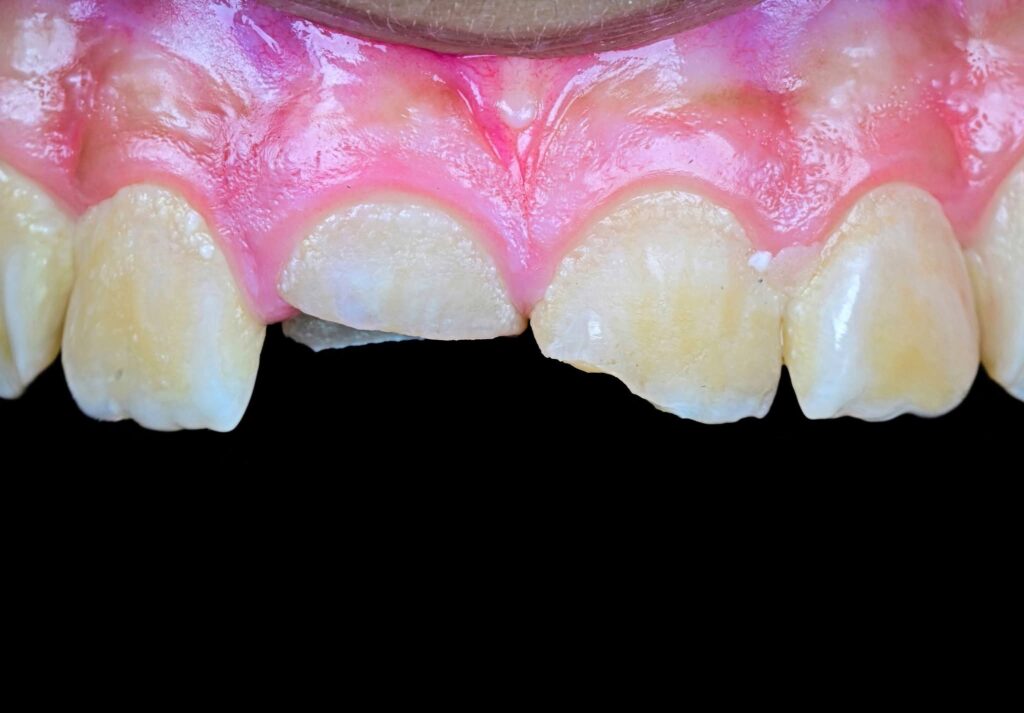

Symmetry and proportionality are fundamental principles in aesthetic dentistry, particularly in direct composite veneers, where the clinician acts simultaneously as a scientist and an artist. Successful veneers are not determined only by color and shape, but by the harmony between teeth, gingiva, lips, and face.

Symmetry refers to the mirror relationship between the right and left sides, especially the maxillary central incisors. Absolute symmetry is not always natural; therefore, perceived symmetry is more important than mathematical symmetry. Small differences in line angles, embrasures, and incisal edges can be used intentionally to create a natural appearance.

Proportionality relates to the width-to-length ratio and the relationship between anterior teeth. The ideal width/length ratio for central incisors is approximately 75–80%, and the apparent width proportion between anterior teeth often follows the golden proportion (~62%), although modern aesthetic dentistry prefers the concept of Recurring Esthetic Dental (RED) proportion for more natural results.

Direct composite veneers require a balance between mathematical proportions and artistic perception. The most aesthetic result is achieved not by perfect symmetry, but by natural, harmonious asymmetry combined with correct proportions.